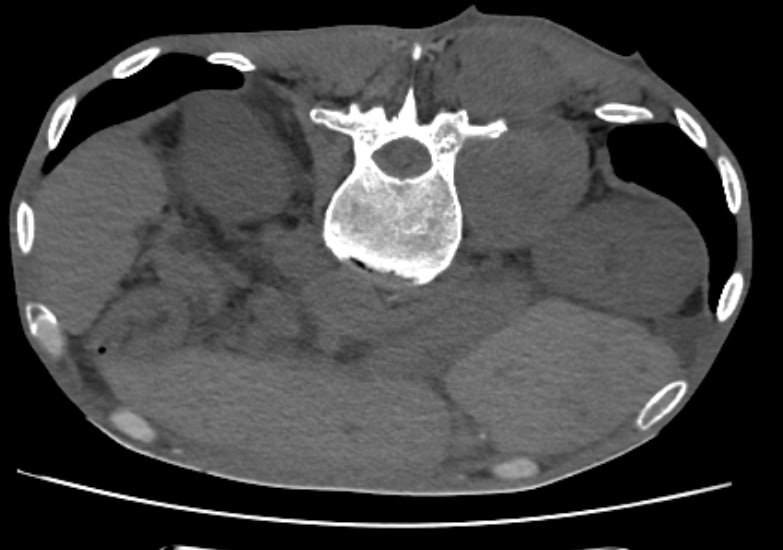

2025 он буюу энэ онд Улсын Хоёрдугаар төв эмнэлгийн Ангиографийн тасаг хөх, уушги, бөөр, ясны хорт хавдрын үед хийгддэг хөлдөөх эмчилгээ буюу CRYOABLATION эмчилгээг нэвтрүүлэн эхлүүлжээ.

Энэ талаар УХТЭ-ийн Дүрс оношилгооны төвийн дарга Б.Эрдэнэбулган "Хорт хавдар ясанд үсэрхийлсэн үед өвдөлт маш их байдаг бөгөөд ялангуяа эмийн эмчилгээнд намдахгүй байгаа өвдөлтийн үед хийхэд өвдөлтийг бүрэн намдааж хавдрын ургалтыг зогсоосон сайн туршлага хуримтлуулж байна.

Мөн энэ эмчилгээ уушги болон бөөрний хорт хавдрын үед голомтыг хөлдөөхөд үр дүн сайтай байдаг. Үүнийг нотолсон маш олон судалгааны ажлууд байгаа. Цаашид энэ төрлийн эмгэгтэй хүмүүст тус хүргэх бүрэн боломжтой боллоо" гэв.